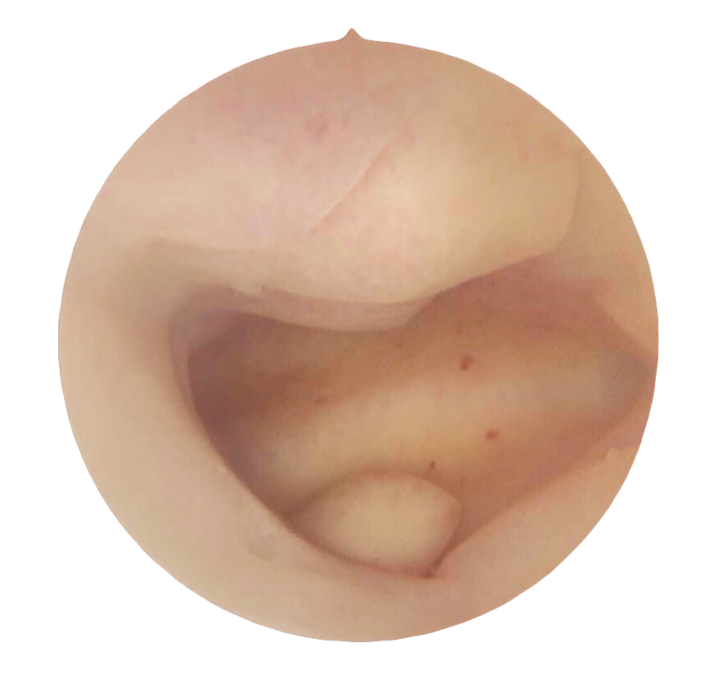

Notre toute dernière génération de lentilles, conçues pour tirer pleinement profit de la HD, procure des images riches, parfaitement résolues, même en périphérie. Cette hyper-résolution, couplée à une lumière répartie de manière véritablement homogène, est gage d’une très grande profondeur de champ. Vous serez «net partout» ! Notre hystéroscope HD est bien entendu autoclavable. Sa conception sous forme de trois tubes distincts le rend résistant, durable mais aussi aisément réparable en cas d’accident.